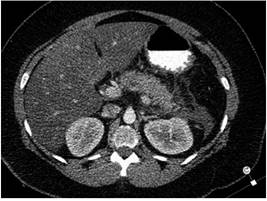

Posteriormente, se procedió a realizar tomografía axial computarizada (TAC) de abdomen contrastada (Figuras 1 y 2) que reportó pancreatitis Baltazar D, permitiendo la reestratificación a pancreatitis Marshall 1 Baltazar D, APACHE-II: 20 (mortalidad: 35%) con criterios de pancreatitis severa e indicación de traslado a la unidad de cuidados intensivos (UCI). Adicionalmente, se complementaron los estudios con perfil metabólico para aclarar la etología con resultados de TAG en 18 060 mg/dL y hemoglobina glucosilada (HbA1c) en 9,87.